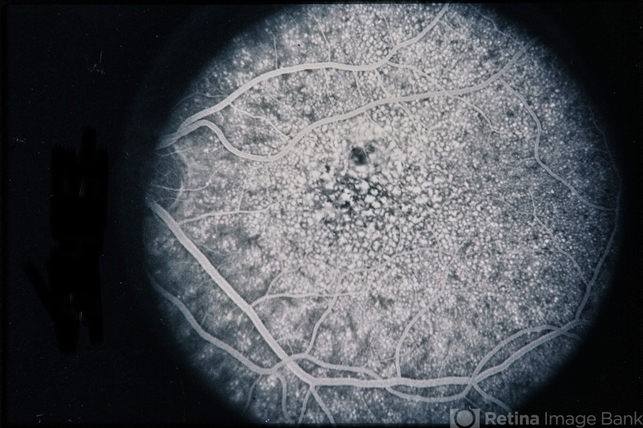

Basal Laminar Drusen Cuticular

basal laminar drusen, cuticular drusen

45-year-old male with basal laminar drusen / cuticular.